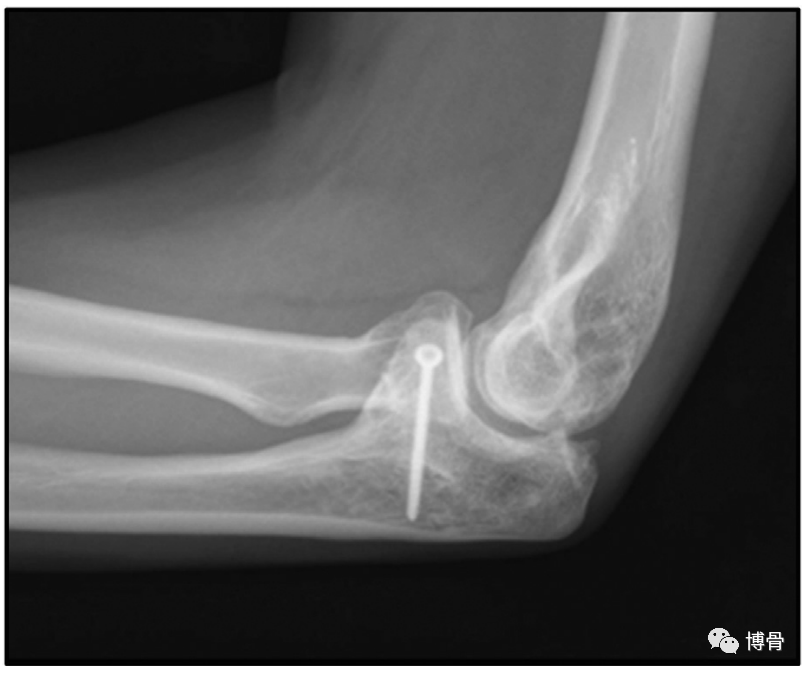

自体髂骨重建冠状突,术后16月X线片示移植物愈合良好